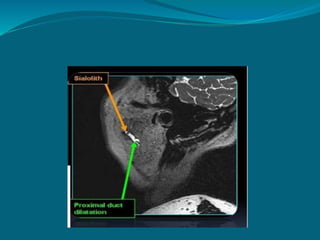

MR sialography

 MRI with evoked

salivation.

 Lemon juice – stimulate

 Reveal ductal morphology

accurately ,sialolith

identification

 Alternative to conventional

sialography.